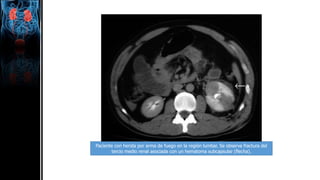

Paciente con herida por arma de fuego en la región lumbar. Se observa fractura del

tercio medio renal asociada con un hematoma subcapsular (flecha).

Paciente con heridapor arma de fuego en la región lumbar. Se observa fractura del tercio medio renal asociada con un hematoma subcapsular (flecha).